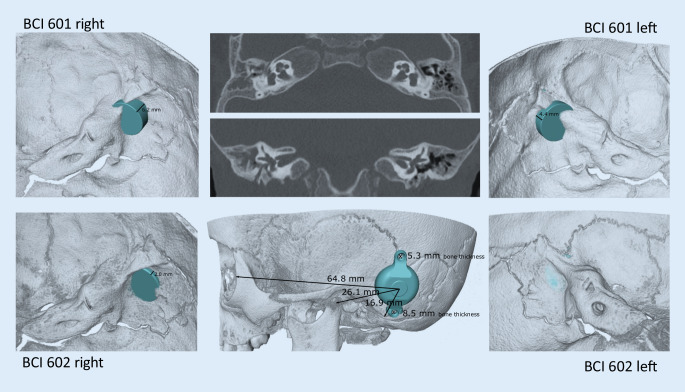

Figure 7 shows the preoperative planning for implanting bone conduction hearing systems in a 4.5-year-old patient with atresia (ear canal stenosis, malformation of the malleus and incus, and a thickened stapes footplate) and complete conductive hearing loss. The parents declined the offer to continue hearing rehabilitation with a soft-band bone conduction hearing aid or canaloplasty with tympanoplasty. Preoperative 3D planning was performed without BC Lifts, since lifts would further elevate the BC-FMT over the bony surface, a feature the authors like to avoid, particularly in the presence of thin skin, which is common in children.

Fig. 7.

Preoperative plan for the implantation of an active, transcutaneous bone conduction hearing system in a 4.5-year-old patient with atresia and complete conductive loss (according to Plontke et al. 2014 [17]). The bone conduction-floating mass transducers required intracranial penetrations of: (A, B) 6–7 mm for the BCI 601 and (C, D) <2 mm for the BCI 602. Due to the expected skull growth [25], a computed tomography scan and planning were not repeated before surgery at the age of 5.5 years. Intraoperatively, the dura and sigmoid sinus were exposed, but not impressed. This patient is also shown in Fig. 4

With the new active BCI and its optimized geometry, the anatomical indication range has significantly increased compared to the previous model (BCI 601). A study that performed “virtual surgery” in 151 temporal bones of 81 children and young adults (ages 5 months–20 years) demonstrated that, in all patients aged 12 years and older, the BCI 602 could be completely fitted to the bone. In patients aged 3–5 years, the BCI 602 could be fitted to the bone in 75% of cases. In contrast, a complete bone fit was not achieved with the BCI 601 in any of the temporal bones without BCI lifts [33]. However, the BCI 602 has not been approved for this age group of up to 5 years. A lower penetration depth would entail a reduced volume of the BC-FMT. However, adequate acceleration of the skull, which is necessary for stimulating the inner ear, would be difficult to achieve. The resonance frequency is indirectly, exponentially related to the mass of the BC-FMT (~m−1/2). Thus, for an electromagnetic transducer with a given mass and resonance frequency, a lower penetration depth required a larger diameter (BCI 601: 15.8 mm and BCI 602: 18.2 mm; Fig. 1). This corresponds to a 15% increase in the diameter and a 45% reduction in the volume of the implant bed. The latter was reached by partially translocating the BC-FMT above the skull surface (Fig. 1). Due to the translocation of the electronics (demodulator) into the BC-FMT, the overall “footprint” of the implant has decreased. Consequently, depending on the individual configuration of the temporal bone, implantation in children under 5 years old appears to be possible and has been performed (off-label) in individual cases (Fig. 10).

Fig. 10.

Preoperative planning based on Plontke et al. 2014 [17] for the implantation of the active transcutaneous bone conduction hearing systems, BCI 601 and BCI 602, in a 3-year-old patient. The patient had bilateral atresia, poorly pneumatized mastoids, hypoplastic tympanic cavities, dysplastic ossicles, an atypical facial nerve course, and complete conductive loss. Without the BCI Lifts, the BCI 601 required intracranial penetrations of 6.2 mm (BCI 601 right) and 4.4 mm (BCI 601 left). The new implant with optimized geometry (BCI 602) required intracranial penetration, with an impression of the dura and/or sinus, of 2 mm (BCI 602right). However, intracranial penetration was completely avoided on the left side by using a 1-mm BCI Lift at the inferior fixation wing (bottom row center). After informed consent about the off-label use in this age group, and due to the explicit wishes of the parents, the BCI 602 was implanted in this patient at the age of 3 years and 4 months (this patient is also shown in Fig. 3). The axial computed tomography (CT) (center top) and coronal CT (center middle) are reproduced with permission from Prof. Dr. S. Kösling (Radiology, University Medicine Halle, Germany)